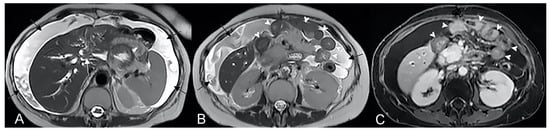

Axial (A) and coronal (B,C) contrast-enhanced fat-suppressed T1-weighted images and axial FIESTA image (E) of the same patient show a complex fistula formed by the intersection of multiple fistulous arms that connect pathological segments of the small intestine to each other and to the ascending colon through the mesentery. These fistulous pathways, intersecting each other, end up taking on the starry appearance, typical of complex fistulas (D).

Crohn’s disease is a common cause of Enterovesical fistula formation. The enterovesical fistula represents an abnormal connection between the enteric lumen and the bladder. Coronal fast imaging employing steady-state acquisition (FIESTA) images (A) show a complex fistula with one arm consisting of an enterovesical fistula (yellow arrowheads). Axial (B) and sagittal (C) T2-weighted MRE image of the same patient shows enterovesical fistula. In (A), inguinal hernia indicated by the blue arrow with involvement of a pathological section of the small intestine.

2.3. Inflammatory Mass or Inflammatory Conglomerate (Aka “Phlegmon”)